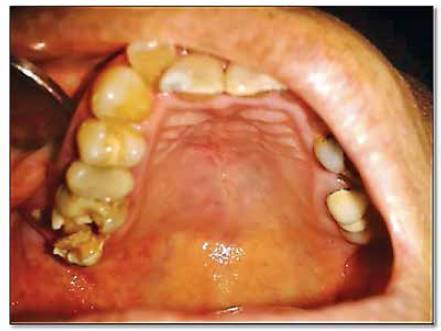

Durante la inspección intrabucal, la lesión se encontró firme a la palpación, indolora y en gran parte de la mucosa se observa de color rosa pálido, otras zonas presentan telangiectasia, irritación y leve inflamación (figura 2). Las piezas molares del cuadrante superior derecho, particularmente la tercera molar, han sido desplazadas hacia vestibular por el crecimiento de la lesión. La mucosa retromolar presenta marcada en su superficie la cara oclusal de la tercera molar inferior derecha, debido a que esta ocluye contra la mucosa, tanto por el tamaño de la lesión como por el desplazamiento que ha ejercido sobre las piezas dentales superiores.

Figura 2 Fotografía intrabucal que muestra la extensión de la lesión. Nótese marcada en la mucosa la cara oclusal de la tercera molar inferior derecha.